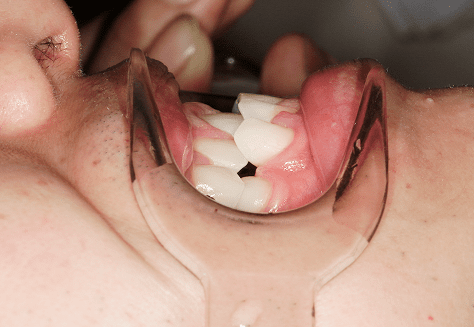

M.M

治療前

治療後

主訴

嚙み合わせが悪い。八重歯が気になる。

診断

叢生・反対咬合

年齢/性別

10代/女性

抜歯部位

非抜歯

使用装置

インビザラインファースト→インビザラインフェーズⅡ(部分的にワイヤーにて処置)

保定装置

上下ビベラリテーナー

診察料金

ファースト時:0円×16回

フェーズⅡ時:5,500円×9回

ワイヤー併用時:8,800円×2回 -

治療期間

2年7カ月